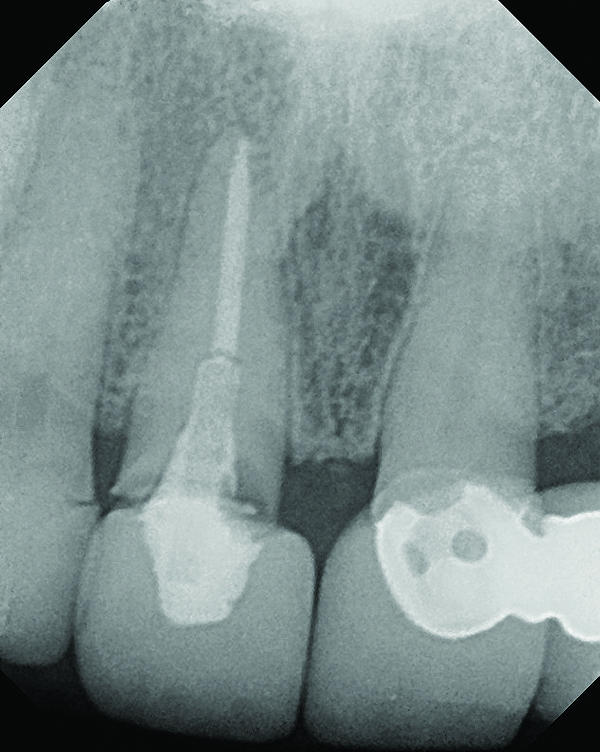

A 63-year-old female patient presented with mobility of her right maxillary incisor, tooth No. 8, secondary to endodontic therapy (Figure 1). Her medical and dental histories were non-contributory. Clinical and radiographic evaluations revealed an 8-mm probing depth on the palatal aspect. The tooth was deemed to be fractured (Figure 2). The treatment plan accepted by the patient was for extraction, immediate implant placement, and immediate provisional restoration, if possible.

The master cast and abutment were returned to the laboratory for fabrication of the restoration (Figure 15). An all-ceramic crown (e.max®, Ivoclar Vivadent) was fabricated on the custom abutment; it matched the contours of the adjacent central incisor. After completion of custom shading, the definitive abutment and crown were returned to the restorative dentist. The abutment was tried in (Figure 16), and a radiograph was taken to confirm complete seating between the abutment/implant and the crown/abutment. The definitive abutment screw was torqued to 20 Ncm, and the screw-access opening was blocked out with Teflon tape.

Fig 2. Periapical radiograph revealing the fractured central incisor.

Figure 2

Fig 18. Radiograph taken immediately after placement of the definitive crown confirmed complete removal of all the cement.

Figure 18